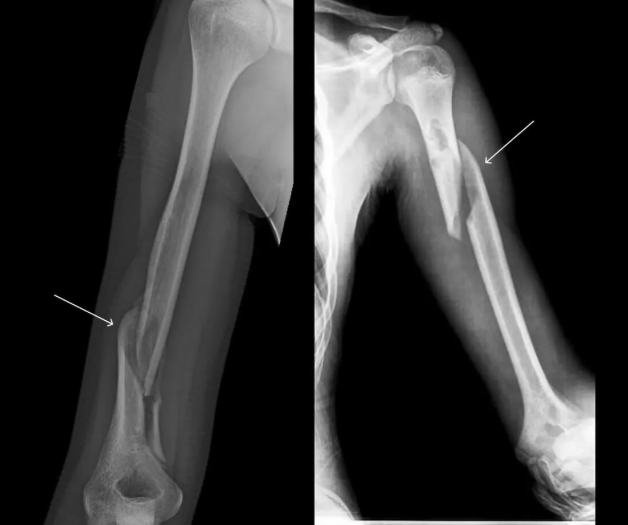

Süňk we bogun inçekeseli.

Süňk skeletinden geçýän keseller

Öýkenden daşky inçekesel